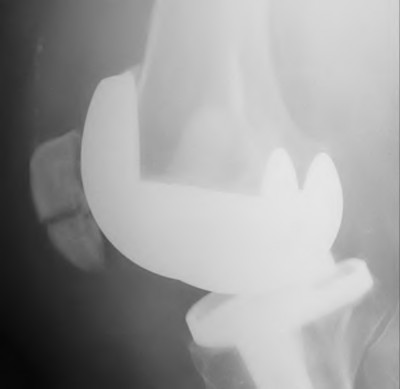

Elevation of the joint line during TKA (often resulting from excessive distal femoral resection and using a thicker polyethylene insert) most commonly leads to which of the following complications?

Explanation